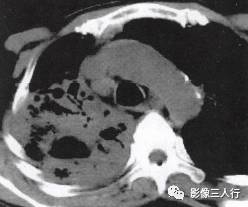

胸部CT图像显示,在含气少的致密肺的背景上见到含气的支气管,表现为两种形态: ①在大片肺实变病灶内的细条状空气密度影;②直径Imm的小泡状空气密度影,连续的几 个层面都能出现(图2、图3)。该征象表明:①近侧气道通畅;②肺泡内的空气经吸收(肺不张)或取代(肺炎、肺癌),或两者综合而消失。通畅含气的支气管在肺泡实变高 密度区内表现为管腔内低密度充气轮廓。